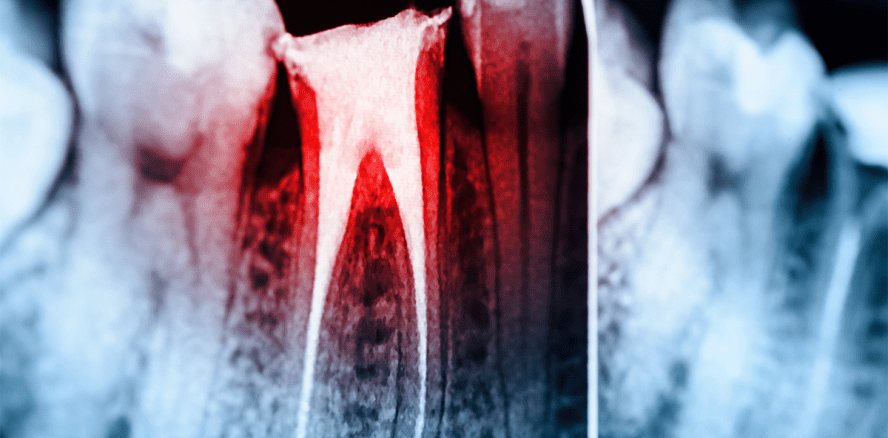

Tod nach Wurzelbehandlung: Junger Patient stirbt in Zahnarztpraxis

Foto: © radub85 – Fotolia.com